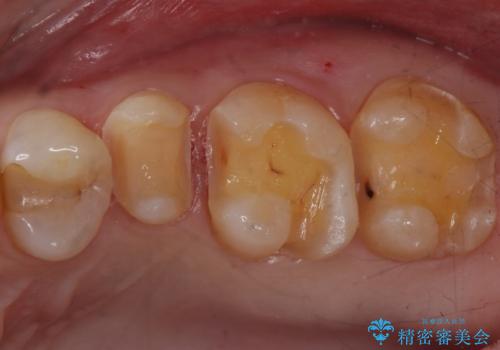

- 銀歯のやり替えをご希望で来院されました。

虫歯を取りつつ銀歯を外し、セラミックインレーでの修復処置を行います。

処置中に手前の歯の詰め物の不適合が確認されたため、追加で治療していくこととなりました。